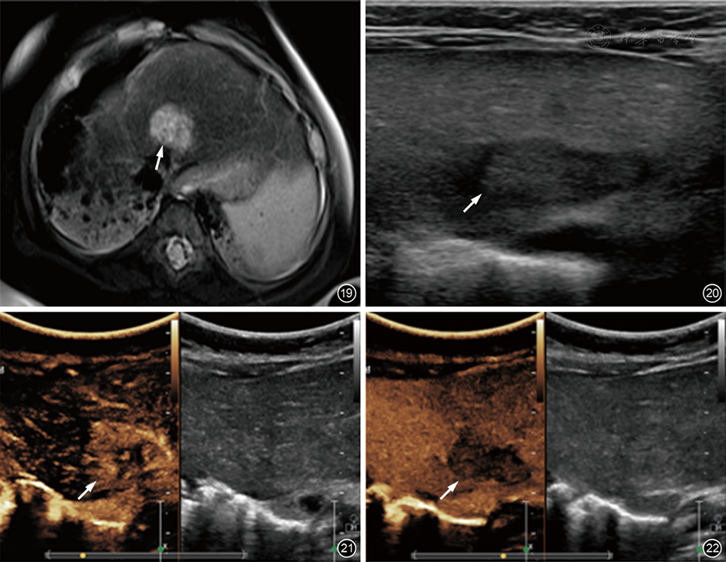

图19~22 患儿女性,6个月,肝母细胞瘤MRI及超声影像图。图19为T2加权MRI示肝内肿块(箭头所示)呈高信号;图20灰阶声像图示肝内肿块(箭头所示)回声不均匀;图21,22为造影增强超声图像(左)和灰阶声像图(右)示肿块(箭头所示)在动脉相(图21)周围性增强和静脉相(图22)的造影剂廓清